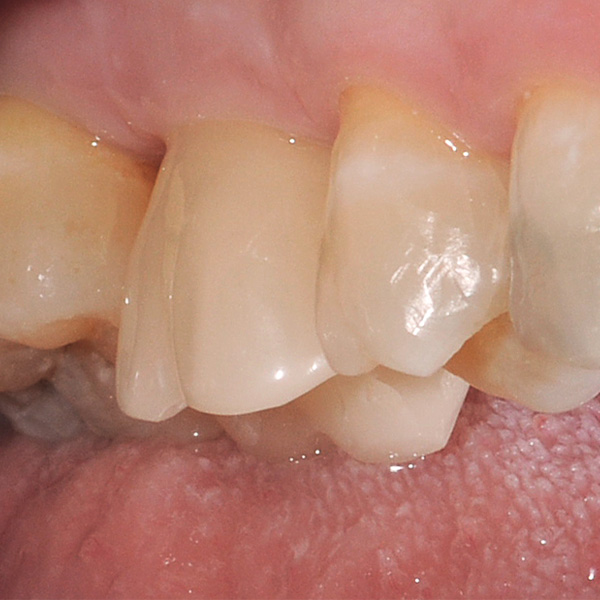

Restaurationen auf Implantaten sind besonders hohen Belastungen ausgesetzt. Da dem Patienten der elastische Faserapparat des natürlichen Zahnbetts fehlt, werden Kaukräfte nicht absorbiert, sondern direkt auf die Restauration, das Implantat, den Knochen sowie die Gegenbezahnung übertragen. Die Hybridkeramik VITA ENAMIC verfügt über eine duale Netzwerkstruktur aus Keramik und Polymer. Daraus resultieren eine dentinähnliche Elastizität und die Fähigkeit, Kaukräfte zu absorbieren. Der mehrfarbige Rohling VITA ENAMIC multiColor in der Geometrie EMC-16 ermöglicht aufgrund seiner hohen vertikalen Dimension auch bei atrophiertem Knochen die Herstellung einteiliger, monolithischer Abutmentkronen. Zahnarzt Professor Dr. Alexander Hassel zeigt im folgenden Beitrag, wie er eine Patientin mit dieser Restaurationsform versorgt.